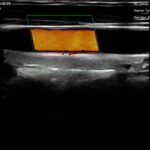

El escáner de ultrasonido portátil de doble sonda es una solución avanzada diseñada para ofrecer máxima versatilidad clínica en un solo dispositivo. Gracias a su tecnología integrada, combina tres modos de escaneo —convexo, lineal y phased array— permitiendo evaluar estructuras profundas, tejidos superficiales y realizar estudios cardíacos con alta precisión. Esta integración reduce significativamente los costos al reemplazar la necesidad de adquirir múltiples sondas por separado.

| Ángulo/longitud de escaneo | Convexo 60, Lineal 40 mm |

| Frecuencia | Sonda convexa de 3,5/5,0 MHz, sonda lineal de 7,5/10 MHz |

| Profundidad de la pantalla | Convexo 90 ~ 305 mm, Lineal 20 ~ 100 mm |

| Función de asistencia en caso de pinchazo | Línea guía de punción en el plano, línea guía de punción fuera del plano, mejora de la aguja |

Lineal: 40 mm

Lineal: 7,5 / 10 MHz

Lineal: 20 – 100 mm

Línea guía en plano

Línea guía fuera de plano

Mejora de aguja